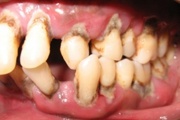

Agressiivne parodontiit

Seda parodontiidi vormi esineb umbes1%-l elanikkonnast. On haiguse kiiresti progresseeruv vorm, mille puhul patsiendid kaotavad kõik hambad enne30-35. eluaastat. Tavaliselt haigestutakse piimahammaste lõikumise ja puberteedi vahele jääval perioodil. Jagunemine:- lokaliseeritud agressiivne vorm- Loe edasi »